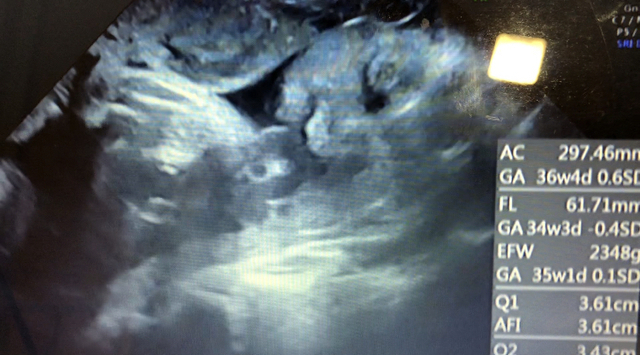

35週0日(35w0d・男の子)|nsa さん(37歳)

エコー写真撮影時のエピソード:

今までパパが見ていた時は、お鼻しかみせなかったのが、今回目も鼻も口もわかり、手で顔を隠してます!エコー動画では、寝てるのに口をパクパクしていて、3か月入院しているので、子供への実感がすごくわかったみたいです。食事は、制限が無いので、食べれる物をたべてます。